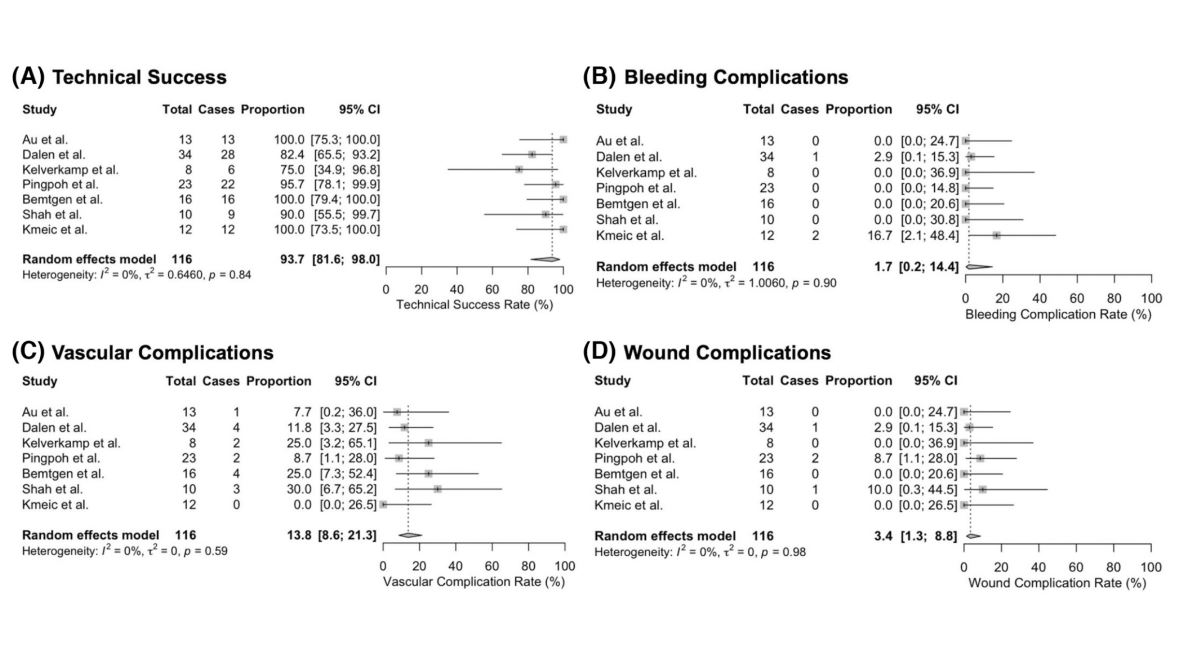

Two reviews in press Seminars in Vascular Surgery : great team work to summarize state of the art and potential of AI in vascular surgical practice sciencedirect.com/journal/semina… Juliette Raffort-Lareyre Jonathan Boyle Arindam Chaudhuri GermanVasc@CA_Behrendt CHU de Nice Hôpital d'Antibes @3IAcotedazur Caitlin Hicks MD, MS